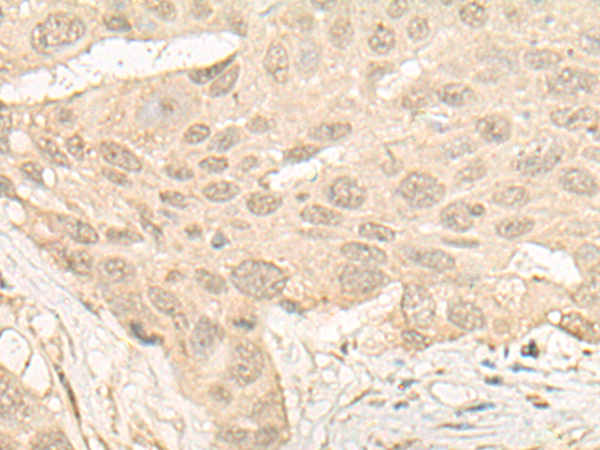

分类: 科研抗体货号: P09634别名: HEL-S-98n应用: WB,IHC反应种属: Human

分类: 科研抗体货号: P09616别名: DEM1; Exo V; hExo5; C1orf176应用: IHC反应种属: Human, Mouse

分类: 科研抗体货号: P09648别名:应用: WB,IHC反应种属: Human

分类: 科研抗体货号: P09632别名: VIB1B; PtdInsTP; PI-TP-beta应用: WB,IHC反应种属: Human, Mouse, Rat

分类: 科研抗体货号: P09615别名: SGD; DAGD; 35DAG; CMD1L; SGCDP; SG-delta应用: WB,IHC反应种属: Human, Mouse

分类: 科研抗体货号: P09647别名: CGI-25应用: IHC反应种属: Human, Mouse

分类: 科研抗体货号: P09631别名: ELA3; ELA3A应用: IHC反应种属: Human

分类: 科研抗体货号: P09614别名: ADL; DAG2; 50DAG; DMDA2; LGMD2D; SCARMD1; adhalin应用: IHC反应种属: Human, Mouse

分类: 科研抗体货号: P09646别名: HLALS应用: IHC反应种属: Human

分类: 科研抗体货号: P09630别名: TSK3; SPOGA3; STK22C; STK22D应用: IHC反应种属: Human, Mouse